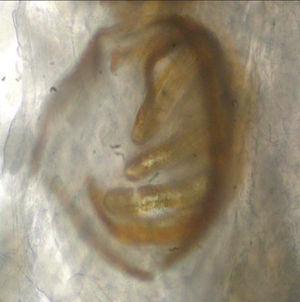

Fig. 4.--Larva Chrysomia.

La identificación de las especies de larvas implicadas fue llevada a cabo por el Servicio de Microbiología del Hospital La Paz, mediante la comparación de cortes de las larvas extraídas fijadas en alcohol con imágenes de atlas de dípteros. Este examen identificó las larvas como pertenecientes al género Chrysomyia en el primer caso (fig. 4) y Sarcophaga en los dos últimos (fig. 5).